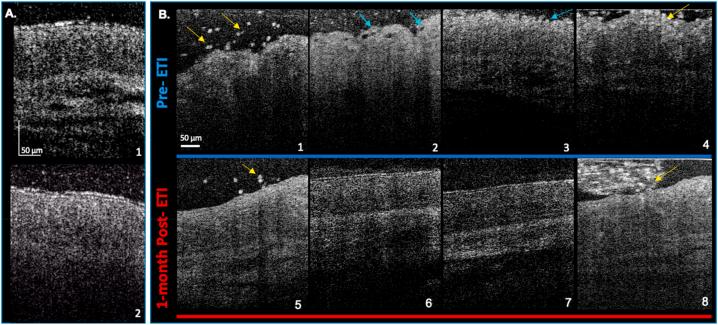

Use of elexacaftor/tezacaftor/ivacaftor (ETI) for treatment of cystic fibrosis (CF) has resulted in unprecedented clinical improvements necessitating development of outcome measures for monitoring disease course. Intranasal micro-optical coherence tomography (μOCT) has previously helped detect and characterize mucociliary abnormalities in patients with CF. This study was done to determine if μOCT can define the effects of ETI on nasal mucociliary clearance and monitor changes conferred to understand mechanistic effects of CFTR modulators beyond CFTR activation.

Percent predicted forced expiratory volume in 1 s (ppFEV) showed a significant increase of +10.9 % at visit 2, which sustained at visit 4 (+10.6 %). Sweat chloride levels significantly decreased by -36.6 mmol/L and -41.3 mmol/L at visits 2 and 4, respectively. μOCT analysis revealed significant improvement in MCT rate (2.8 ± 1.5, visit 1 vs 4.0 ± 1.5 mm/min, visit 2; P = 0.048).

Treatment with ETI resulted in significant and sustained clinical improvements over 6 months. Functional improvements in MCT rate were evident within a month after initiation of ETI therapy indicating that μOCT imaging is sensitive to the treatment effect of HEMT and suggests improved mucociliary transport as a probable mechanism of action underlying the clinical benefits.